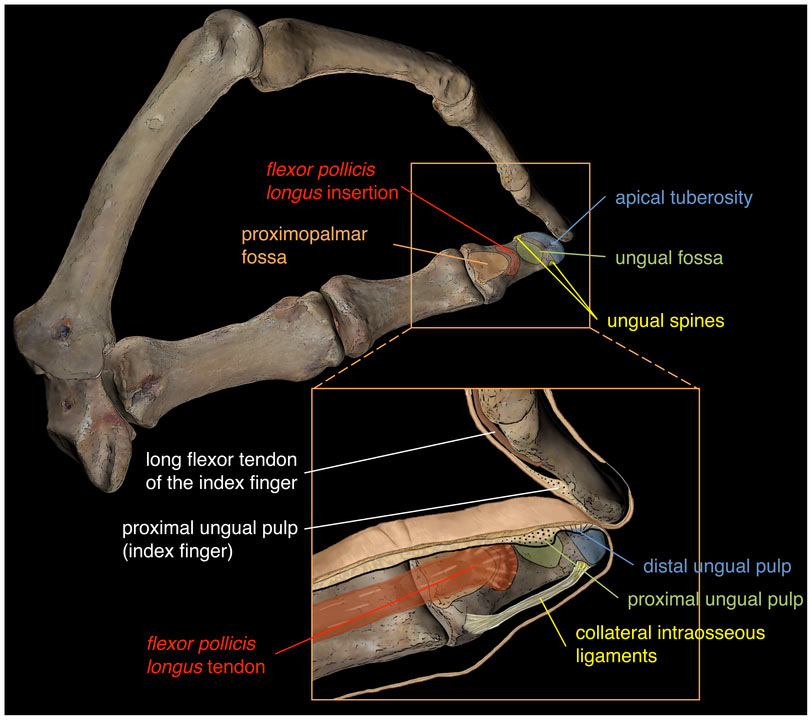

Tanto la porción superficial como la profunda se convierten en una estructura tendinosa. Después de recorrer una parte del camino junto al flexor largo del pulgar, el fascículo profundo termina uniéndose al superficial.

Formando un tendón único, el flexor corto del pulgar se inserta en la base de la falange proximal del pulgar y en el hueso sesamoideo que se encuentra inmerso en los ligamentos que forman parte de esa articulación.